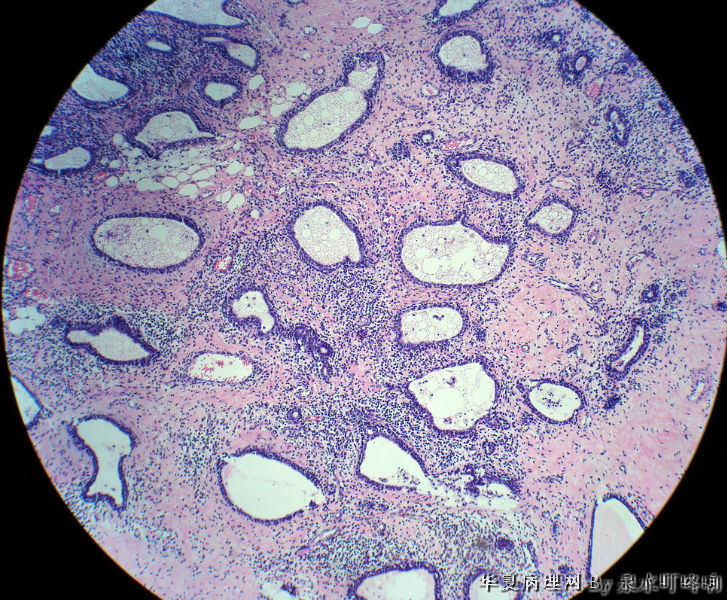

120213,女,23岁,右乳腺肿物半年,术中见肿物为多房性囊性肿物,内容黄色粘稠液体。

大体:灰白囊性肿物一个,大小约3×2×1.9厘米,局部囊壁增厚。

乳腺腺病 导管扩张囊性变 淋巴细胞性乳腺炎